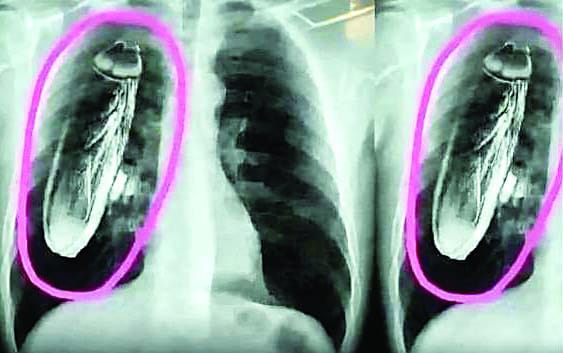

AI X-rays bring disrepute to hospitals across the state, and fake social media posts create panic in Solan, Shimla, and Baddi.

सोशल मीडिया पर पिछले एक-दो दिन से तेजी से वायरल हो रही एक्स-रे कॉपी में दिख रहे कॉकरोच वाली पोस्ट ने लोगों को परेशान कर दिया है। कभी सोलन, कभी शिमला तो कभी बद्दी अस्पताल की कहानी के नाम से डाली जा रही इस पोस्ट ने स्वास्थ्य विभाग को भी पूरा हिला डाला है। स्वास्थ्य विभाग ने इस पोस्ट को लेकर गंभीरता दिखाई है और ऐसी किसी भी घटना का खंडन करते हुए इसे एआई जनरेटेड फोटो करार दिया है। विभागीय अधिकारियों ने लोगों से इस तरह की वायरल पोस्ट से परहेज करने की भी सलाह दी है। सोलन, शिमला और बद्दी के अस्पताल की कहानी लिख वायरल हो रही एक्स-रे कॉपी से लोग परेशान हो गए हैं। इसका प्रभाव अस्पताल में होने वाले एक्स-रे में भी पड़ा है। शुक्रवार देर रात से एक्स-रे कॉपी वायरल हो रही है। क्षेत्रीय अस्पताल में रोजाना से कम एक्स-रे हुए हैं। पोस्ट के वायरल होते ही स्वास्थ्य मंत्री ने भी क्षेत्रीय अस्पाल सोलन प्रबंधन से भी बात की और इसकी सत्यता जानी। सोशल मीडिया में वायरल हुए पोस्ट में तीन एक्स-रे कॉपी लगी है।